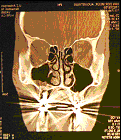

Röntgenfoto’s

Van mijn kaak(bij)holtes ivm amandelontsteking van 1985-1999

Kaakholtes vóór de  keel- en neusamandelenoperatie

Kaakholtes na de  keel- en neusamandelenoperatie